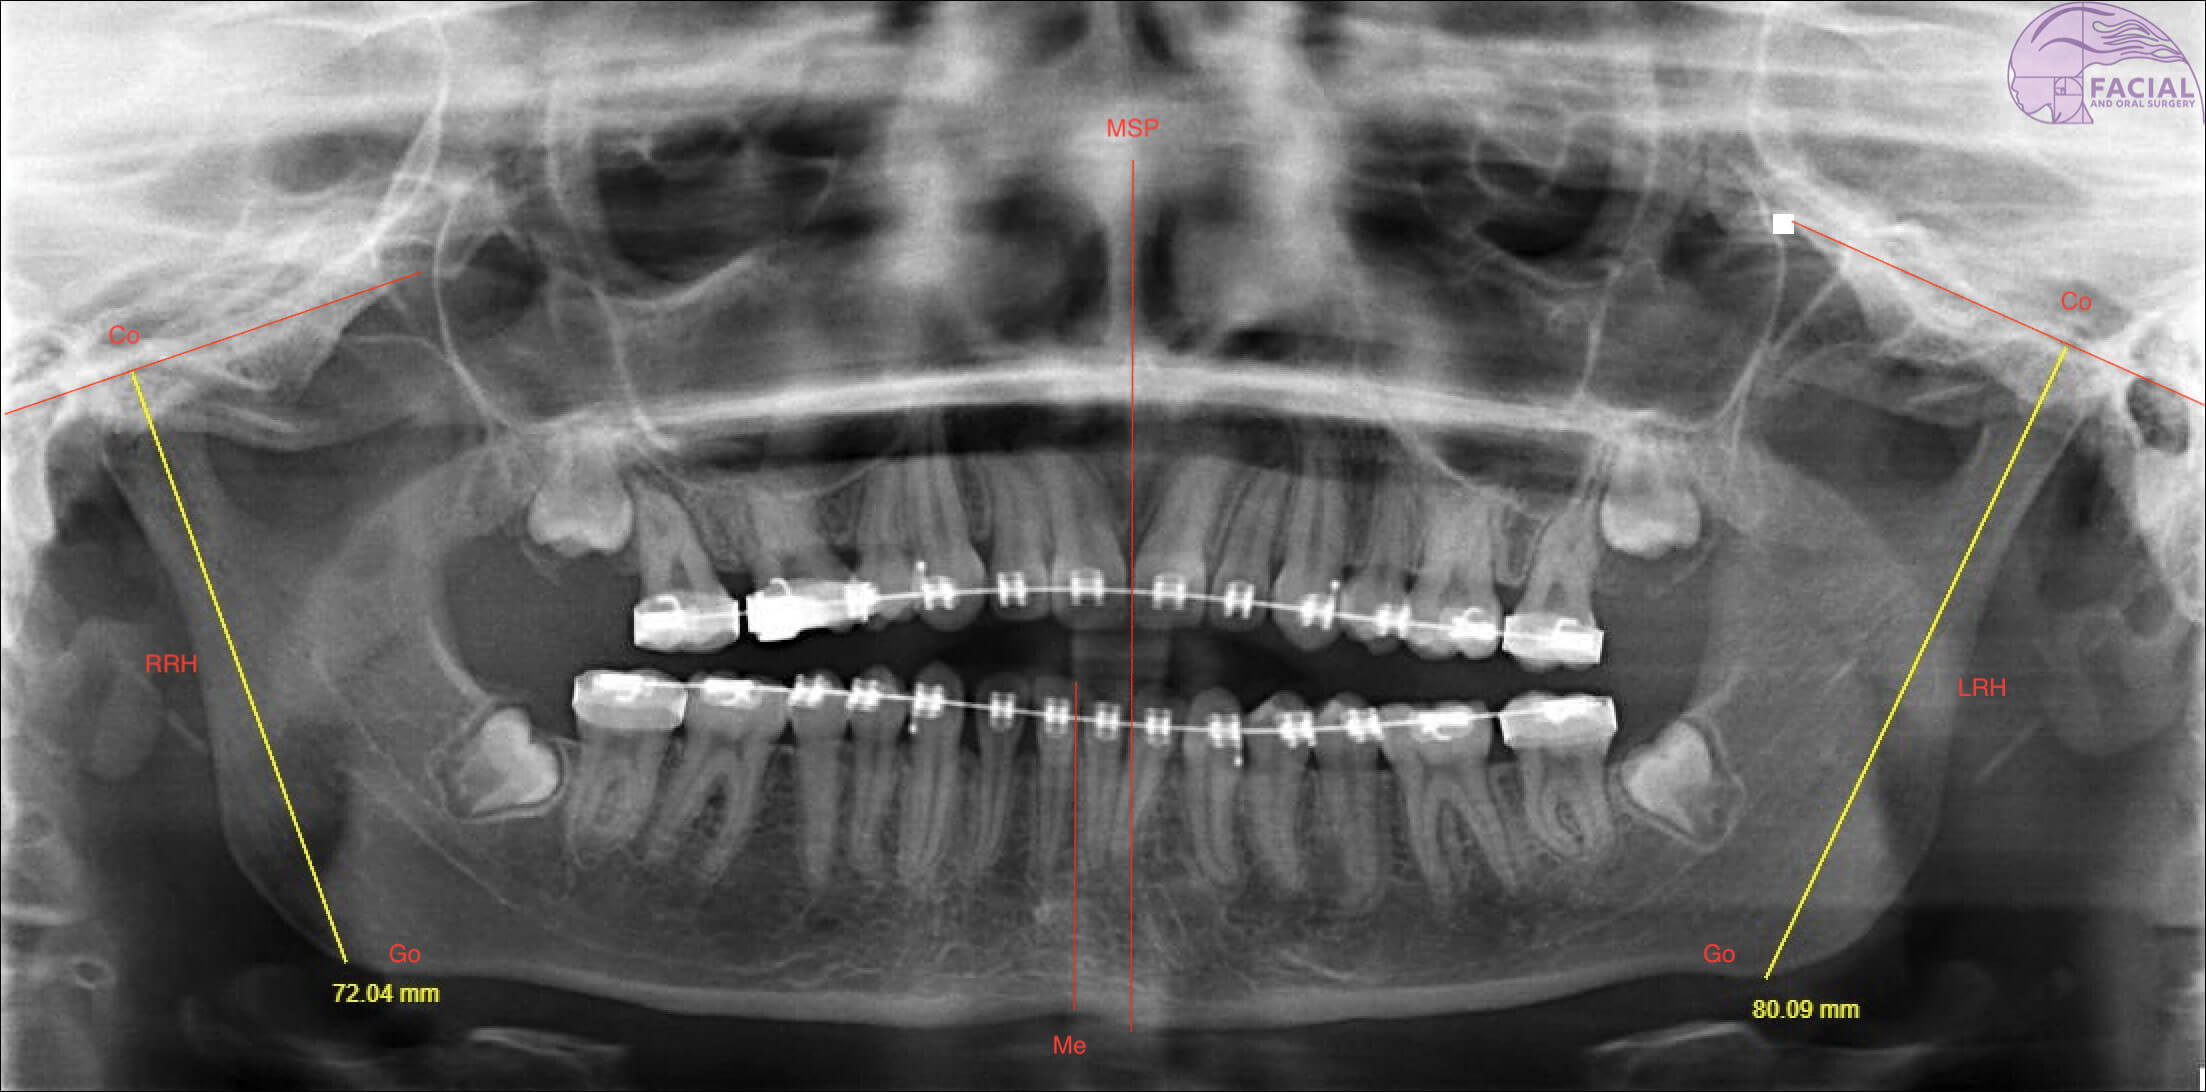

Mandibular asymmetry: Importance of personalised treatment

This article has been verified for CPD. Click the button below to answer a few short questions and download a form to be included in your CPD folder. Human facial symmetry is a key determinant for assessing facial attractiveness, and...